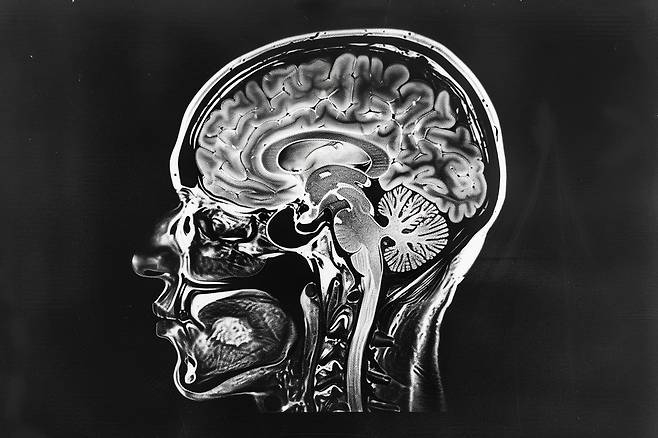

연구팀은 ‘구조적 자기공명영상(Structural MRI)’을 활용해, 참가자들의 편도체, 해마, 꼬리핵, 측핵, 창백핵, 피질핵, 시상 등 뇌의 다양한 영역별 부피를 측정했다. 구조적 MRI는 뇌의 활동을 측정하는 기능적 MRI(fMRI)와 달리, 뇌의 해부학적 구조를 상세하게 보여주기 위한 촬영 방식이다.